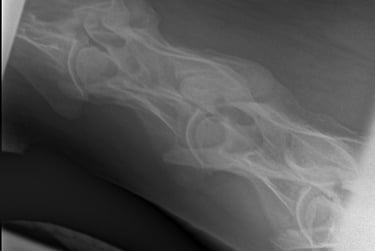

Is uw paard mank, hoefbevangen of is er een vermoeden van een halsprobleem? Dan kan het aangewezen zijn om een radiografisch onderzoek (RX) aan huis uit te voeren. Wij beschikken over een digitaal mobiel radiografietoestel, waardoor opnames eenvoudig bij u ter plaatse kunnen worden gemaakt.

Radiografie (RX)

Consult op de praktijk of aan huis